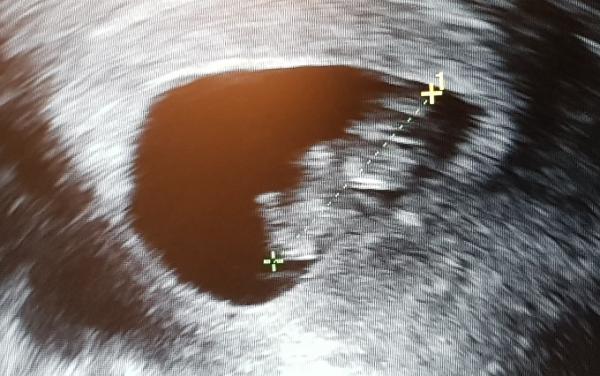

2,5 cm groß, Herztöne super und ein wenig hin und her bewegt hat es sich (bei 9+3).

Leider vorderwandplazenta, aber gibt schlimmeres. Kann sich das nochmal verschieben?